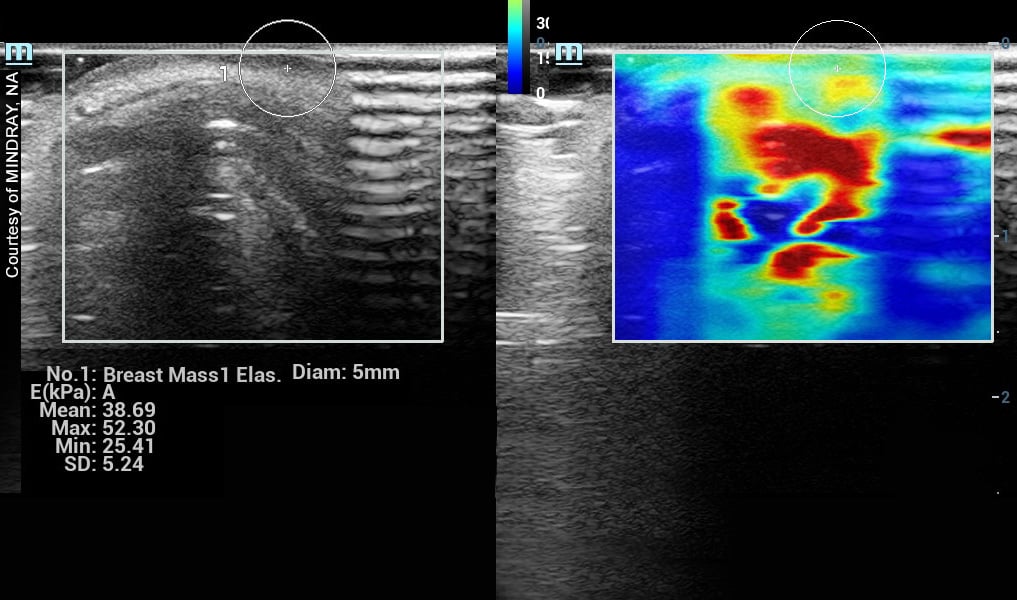

Another example of a dense breast shows the difference between homogeneous white versus the whitish area (see Image 3). This is filled with dark, wormy looking structures, which are the breast glands called glandular tissue. This kind secretes milk and its glands are often dilated. Both fibrous and glandular may appear similar under a mammogram as highly dense areas, but they look completely different under an ultrasound scan. Through ultrasound, we can check for tumors easily through fibrotic dense breasts because it stands out as a black region (or a black hole) within the white area. As shown in Image 3, a black hole could get lost, making it more difficult to image this type of dense breast. In this case, a solution is the use of elastography (see Image 4), which offers visual confirmation as indicated by color data. Elastography can measure tissue density (its hardness or elasticity) within the glandular breast tissue.

Image 4: Elastography of breast mass.